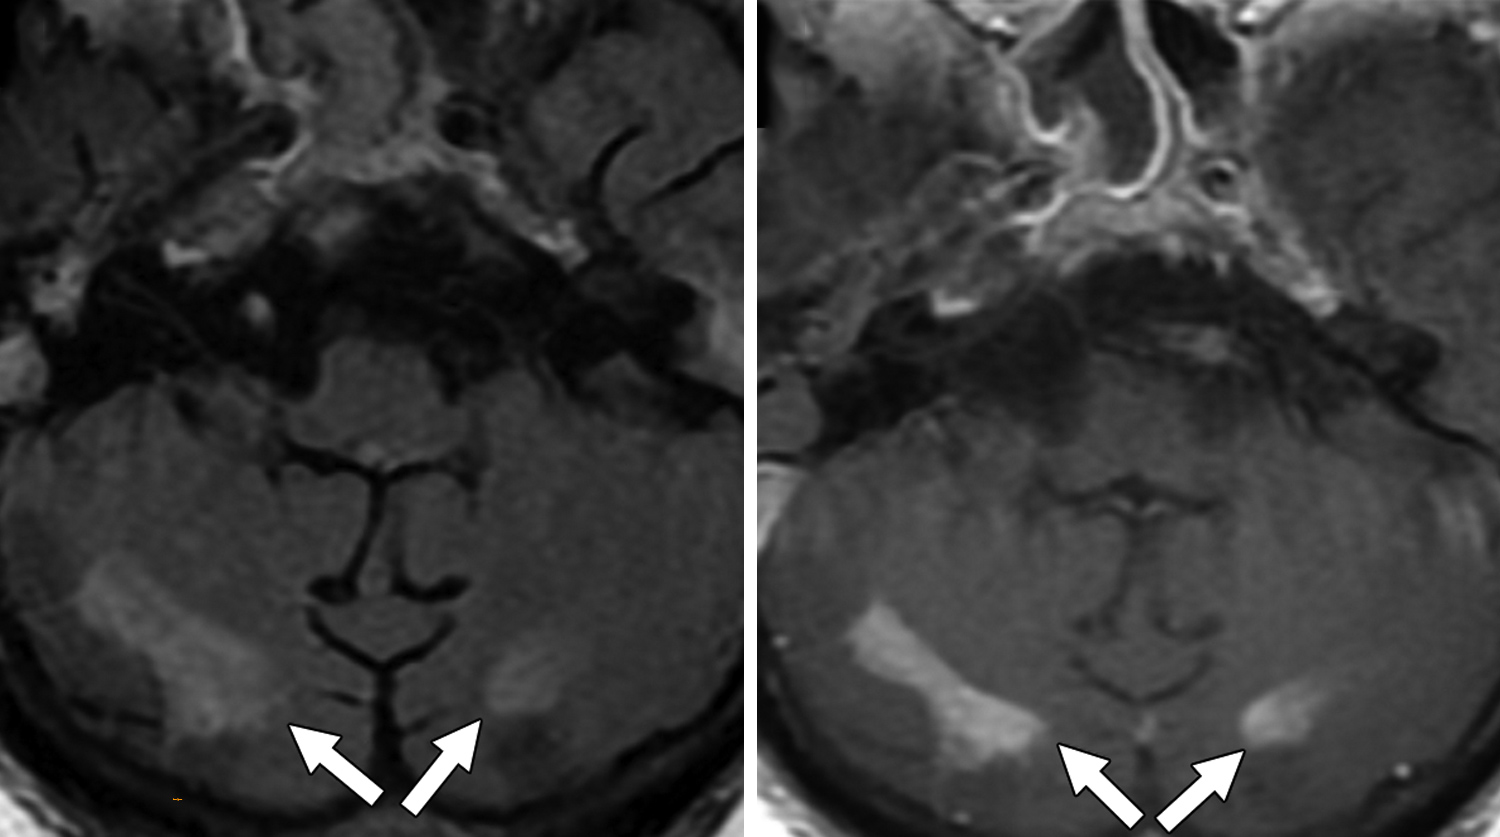

Из 2820 пациентов с COVID-19, с которыми имели дело авторы работы в период с 1 марта по 18 июня 2020 г., 59 прошли МРТ головного мозга. У многих наблюдались признаки поражения мозга, вызванные рассеянным склерозом, инсультами, нехваткой кислорода в крови, недостаточным кровоснабжением мозга и прочими факторами. Но также исследователи заметили, что у шести пациентов (10,2%) имелись признаки лейкоэнцефалопатии.

«Мы наблюдали обширное слияние очагов поражения белого вещества (с характеристиками и расположением, нетипичными для других причин), микрогеморрагическим кровоизлиянием, с ограниченной диффузией, — пишут исследователи.